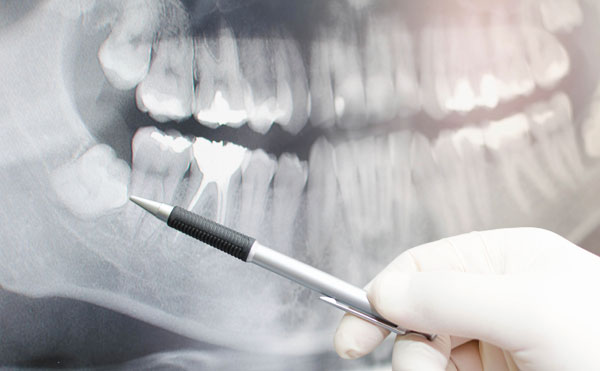

Comprehensive Evaluation / Oral Examination

An oral examination is a visual inspection of the mouth, head, and neck, performed to detect abnormalities. Radiographs allow for a more complete examination, helping the doctor to detect cavities, problems in existing dental restorations, gum and bone recession or other abnormal conditions within the mouth, head and neck area.